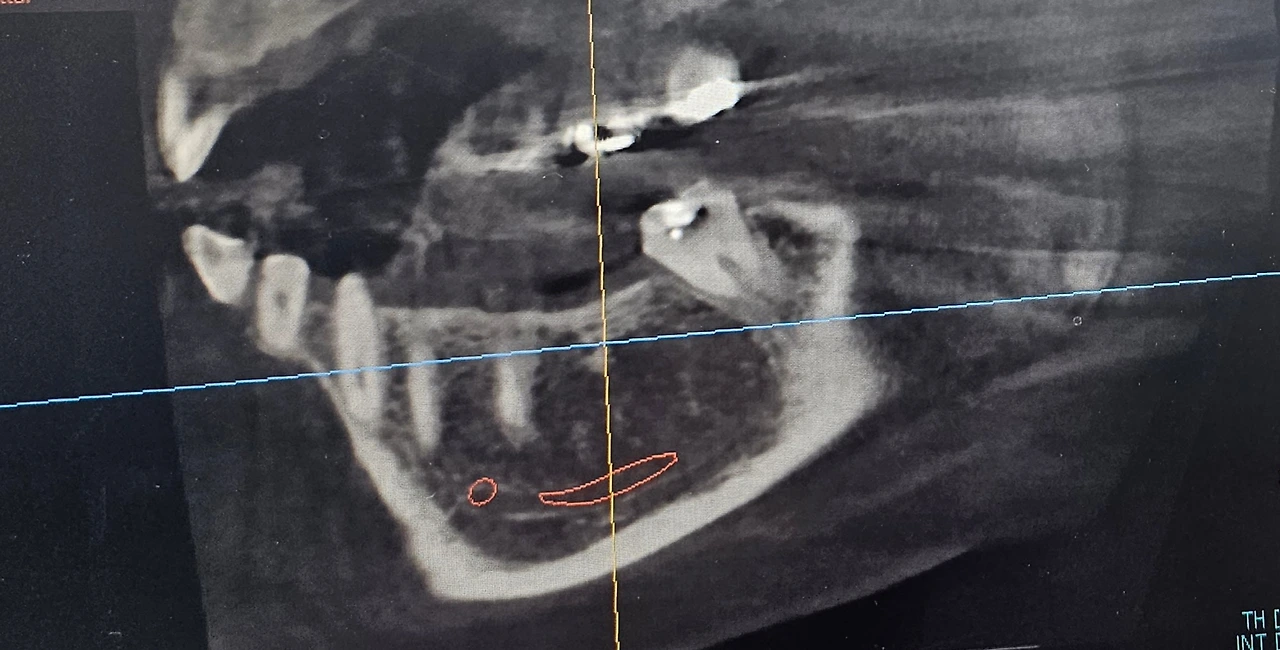

치과를 방문하여 X-RAY촬영을 하고 살펴보았다.

치과 선생님은 사진으로는 알 수가 없고 브릿지를 뜯어봐야 고통의 원인을 알 수 있다고 했다.

결국 선생님은 일단 가운데 치아가 없는 자리에 임플란트를 심어보자고 하였다.

임플란트를 심으면 지지대가 되어 힘을 받게 되어 아프지 않을 수도 있다고 하였다.

임플란트의 재료는 사람의 턱 뼈와 잘 붙기 때문에 잇몸에 심어 두었다가 보통은 3개월 정도가 지나면 커플 보철물을 식립하여 정상의 치아처럼 사용할 수 있다고 한다.